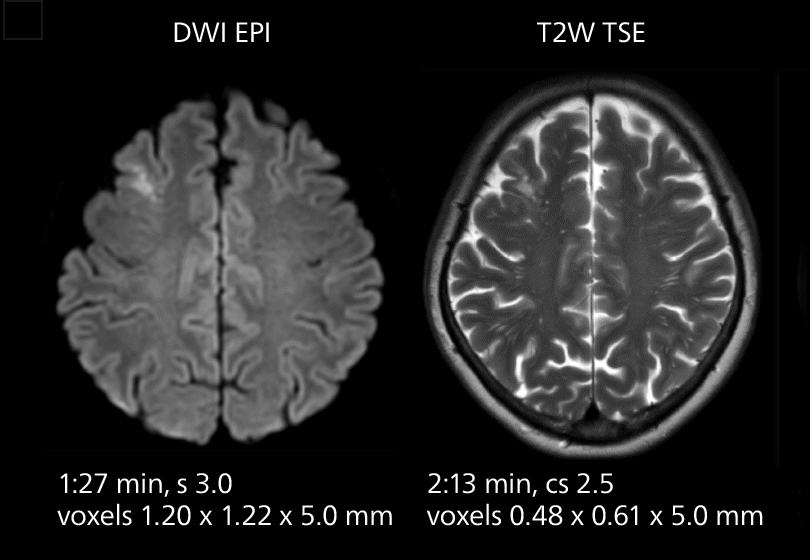

Brain MRI

These images of an old cerebral infarction demonstrate the speed and image quality after upgrading to Elition X.

Brain MRI

These images of an old cerebral infarction demonstrate the speed and image quality after upgrading to Elition X.